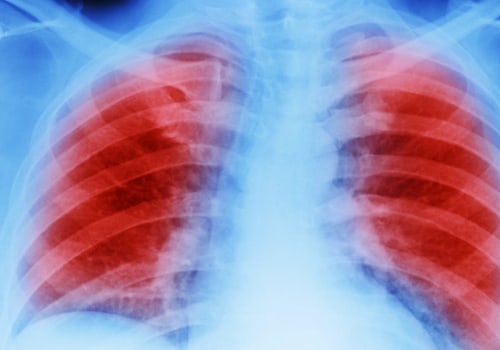

Mesothelioma cancer occurs by inhaling or ingesting asbestos fibers. Asbestos fibers are lodged in the lining of the lungs, abdomen, or heart. Fibers cause inflammation and scarring. Exposure to asbestos can lead to the development of mesothelioma cancer.

We know that asbestos causes most cases of pleural mesothelioma. This starts in the two sheets of tissue that cover the lungs, called the pleura. Being exposed to large amounts of asbestos for a long period of time increases the risk of mesothelioma. Many people with mesothelioma in the abdomen (peritoneal mesothelioma) have also been exposed to asbestos.